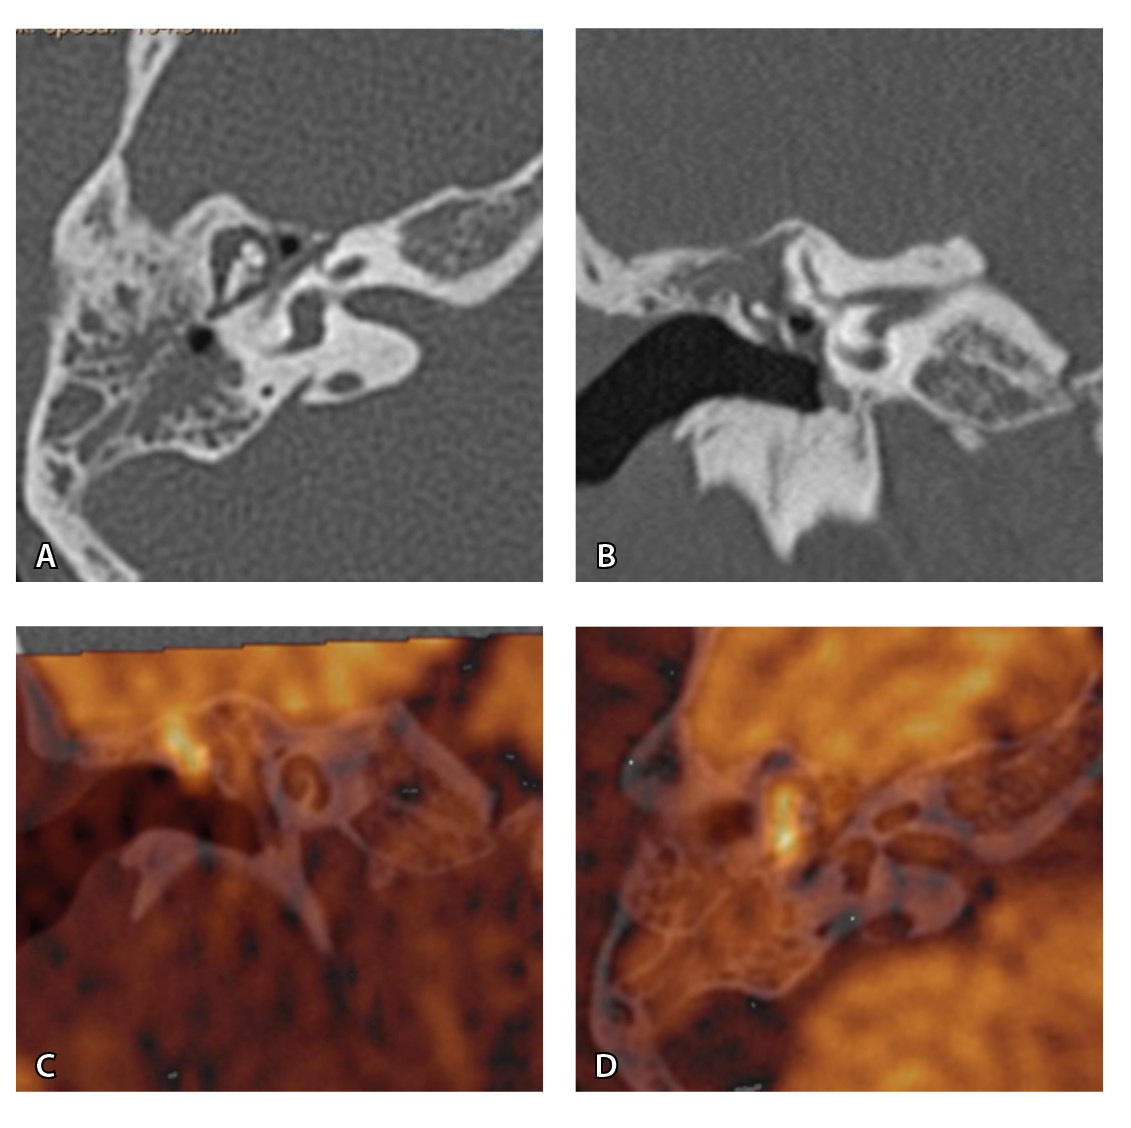

На рис. 3 и 4 показано расхождение данных КТ и МРТ.

Рис. 3. Хронический правосторонний средний отит. По данным компьютерной томографии (А, Б) нет ремоделирования барабанной полости, деструкции и смещения косточек, скутум сохранен, данных за холестеатому нет. При магнитно-резонансной томографии (В, Г) у того же пациента выявлен очаг высокого магнитно-резонансного сигнала, который при слиянии локализовался в области пространства Пруссака. Заключение и интраоперационно – холестеатома пространства Пруссака